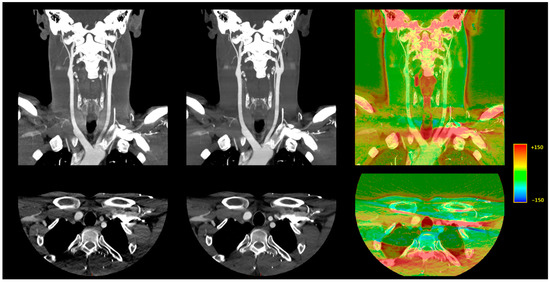

3.3.1. Image Signal Fluctuation with DLR vs. H-IR

3.3.2. Comparison of the Two Reconstruction Techniques at Constant kVp Value

3.3.3. Comparison of Low kVp plus DLR vs. Standard kVp plus DLR

3.3.4. Comparison of Low kVp plus DLR vs. Standard kVp plus H-IR